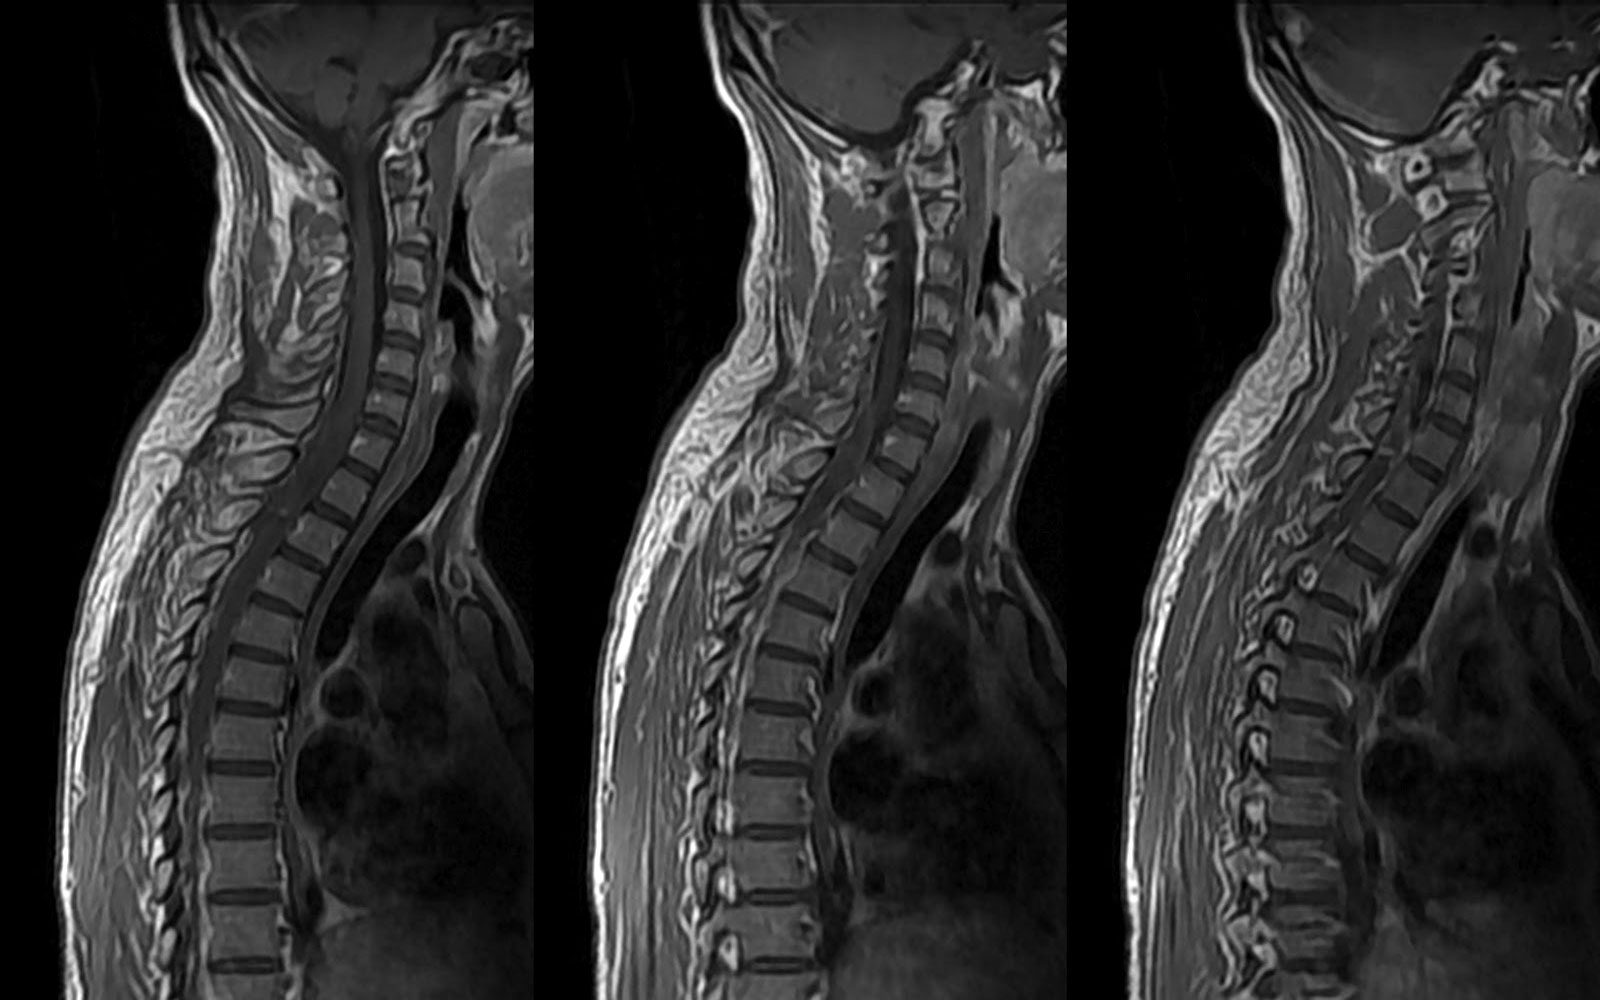

Главный инструментальный метод исследования при туберкулезе позвоночника – это его рентгенологическое исследование:

- рентгенография грудной клетки – на снимках могут быть выявлены первичные туберкулезные очаги во внутригрудных лимфатических узлах, а также в верхних отделах легких;

- рентгенография позвоночника – характерным показателем является стойкое сужение межпозвонковых промежутков на ранних стадиях заболевания и деформация позвонков при прогрессировании патологии. При дальнейшем прогрессировании болезни наблюдается спадание тел пораженных позвонков.

Для получения более детальной информации могут быть привлечены такие методы, как:

- магнитно-резонансная томография (МРТ) – используется для изучения степени поражения связок, а также для выявления натечных абсцессов (гноя, который переместился из первичной локализации);

- компьютерная томография (КТ) – позволяет выявить более глубокие деструктивные процессы в тканях пораженных позвонков.